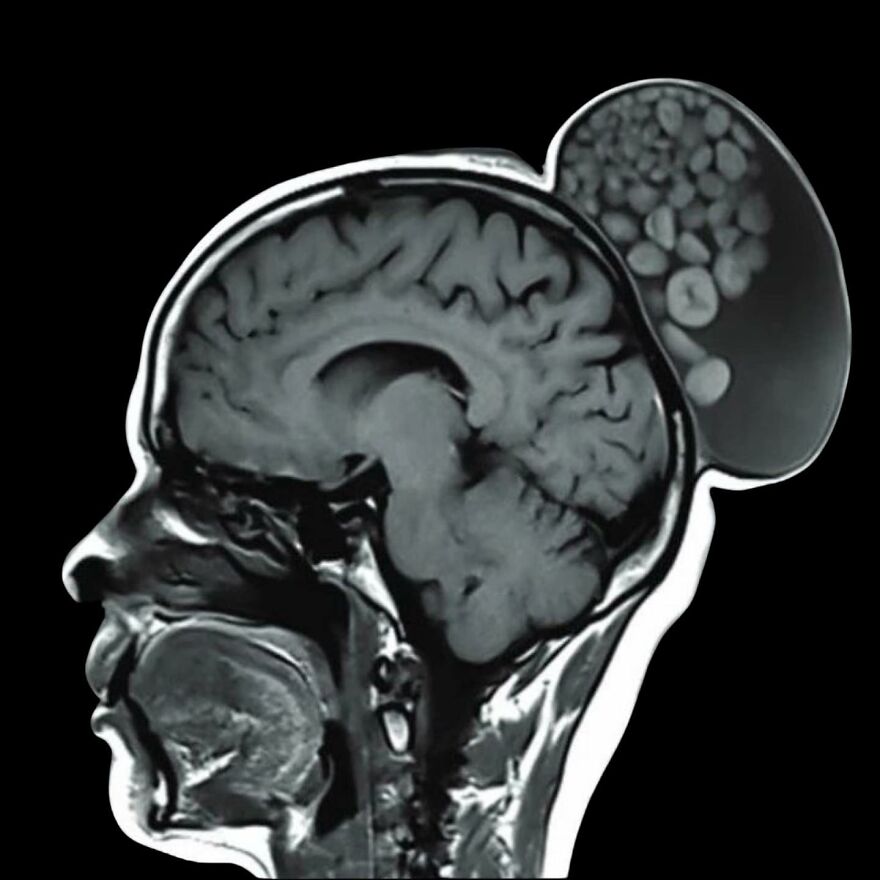

Pri nezvyčajnej operácii lekári v Bengalúre odstránili z hlavy ženy vypuklý výrastok, ktorý pripomínal „vrece s guľôčkami“